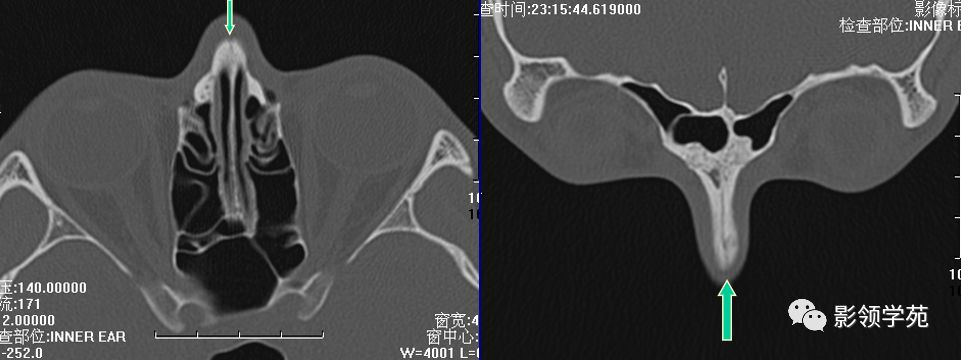

线性骨折 粉碎骨折

右侧鼻骨骨折

左上颌骨额突骨折

双侧鼻骨骨折

双侧上颌骨额突骨折